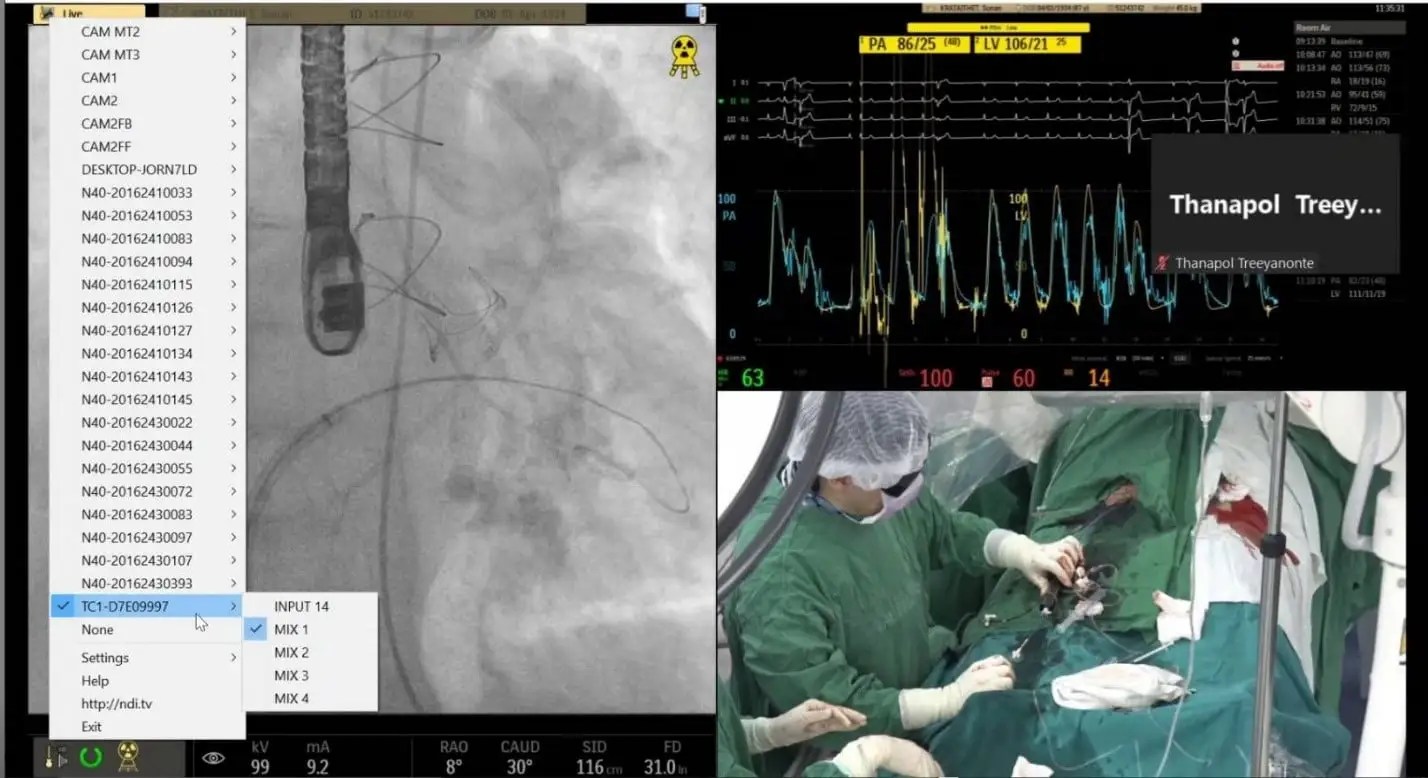

The Hospital has since discovered a completely different approach that enables live video from cameras in the operating rooms to be showcased and streamed, along with readings from the wide array of medical devices simultaneously in use during surgical procedures. Unlike the conference setup, this solution is based upon Vizrt live video production and streaming solutions, such as the TriCaster® TC1 and TriCaster Mini 4K. These easy-to-use video creation systems let anyone—even those lacking specialized video production or IT expertise—produce compelling videos with broadcast-quality results and resolutions up to UHD.

Adding to the user-friendliness of the Vizrt gear is their full support for Network Device Interface (NDI®), an industry standard Video-over-IP networking protocol. NDI enables video transport in real-time over standard gigabit ethernet local area network cabling, the type that’s commonly available at facilities like those at the Hospital. Vizrt video production and streaming solutions work together with NDI to make it relatively simple and cost-effective to produce high-quality video with just a single operator or small video crew. The equipment was purchased from SWS Group Company Limited, a video dealer in Bangkok, Thailand.

With its unique video production setup, the Hospital has strategically positioned NDI-compatible video cameras around two of its operating rooms, with plans to outfit a third in the near future. Using an iPad, laptop, or computer keyboard, video signals from the NDI cameras can be pre-set, controlled, switched, and displayed in the facility’s conference room or incorporated into online meetings via platforms such as Zoom. The video signals can just stream into the TriCaster switchers, or these IP-based tools allow remote control of the cameras, including the pan, tilt, zoom functions, if desired. This is part of their Livestreaming Cardiac Training and Consultations initiative in the Thai hospital.

Data from the medical devices in the OR can also be managed and controlled remotely using the iPad, laptop, or computer interface. The HDMI and DVI outputs of the medical equipment are converted in real-time to NDI—at resolutions up to 4K/60p resolution—using a bio-directional 4K converter to convert these signals to NDI for transmission over the network.